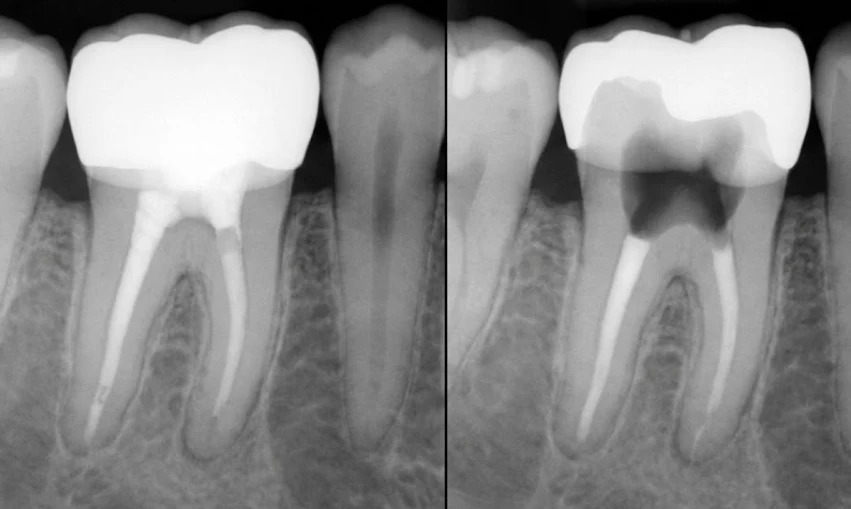

рентген, показывающий скрытый кариес под коронкой

Что обычно происходит: пациент решает пройти стандартное медицинское обследование в Турции и чувствует себя отлично. Однако, даже если Дентолог Полен Аккылынч и её команда не обнаруживают внешних признаков проблемы, рентген показывает, что зуб практически исчез, из-за огромного кариеса. Пока пациент не заметит, что коронка «ослабла» или выпала, кариес почти всегда достиг такого уровня, что зуб больше нельзя спасти ​‍​‌‍​‍‌​‍​‌‍​‍‌.

2. Рентген — обязательно: Так как эти кариесы невидимы невооруженным глазом, вам нужны рентгенологические данные. Мы рекомендуем панорамный рентген как минимум раз в год.